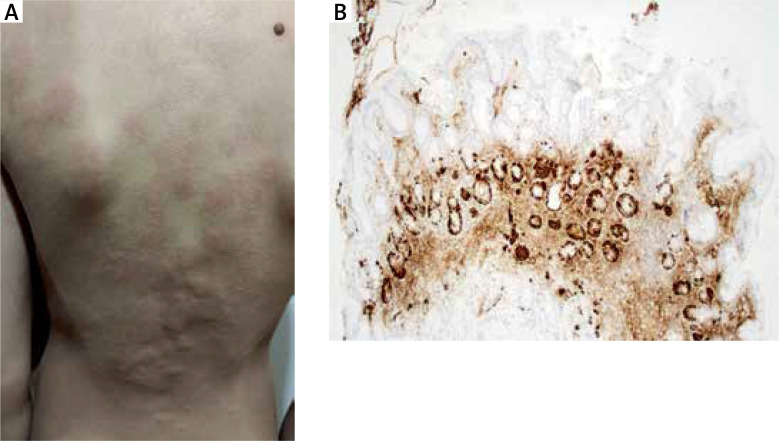

Chronic spontaneous urticaria linked with autoimmune atrophic gastritis in a paediatric patient.

小儿慢性自发性荨麻疹合并自身免疫性萎缩性胃炎1例